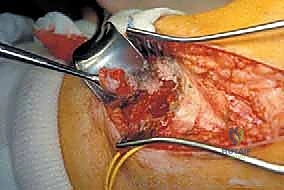

2. الشق الجراحي والوصول (Incision & Exposure)

يقوم الدكتور هطيف بعمل شق طولي على طول الجزء الخارجي من الساق. يتم التخطيط للشق بحيث يشمل ندبة الخزعة السابقة (لإزالتها مع الورم). يتم فصل العضلات بلطف شديد للوصول إلى الشظية.

3. عزل وحماية العصب الشظوي (Nerve Isolation)

هذه هي الخطوة الأكثر دقة وحساسية. باستخدام أدوات الجراحة الميكروسكوبية، يقوم الدكتور هطيف بتحديد العصب الشظوي الشائع، وتسليكه بعناية فائقة، وإبعاده عن منطقة الورم باستخدام أشرطة مطاطية طبية لحمايته من أي شد أو قطع.

يتم تحديد الشريان والوريد الظنبوبي الأمامي والشريان الشظوي وحمايتهم. في بعض الأحيان، إذا كان الورم يحيط بأوعية دموية صغيرة، يتم ربطها وقطعها للتمكن من إزالة الورم بحرية.

5. الاستئصال العظمي بهوامش آمنة (Osteotomy with Wide Margins)

يتم تحديد نقاط القطع على العظم أعلى وأسفل الورم بمسافة آمنة (عادة 2-3 سم من الأنسجة السليمة لضمان عدم ترك أي خلايا سرطانية). يتم استخدام مناشير عظمية دقيقة لقطع الشظية. يتم استخراج الكتلة الورمية كقطعة واحدة (En bloc) مع العضلات المحيطة بها الملتصقة بالورم.

7. الإغلاق ووضع المصارف (Closure)

يتم غسل الجرح بمحاليل معقمة، ووضع أنابيب تصريف (Drains) لسحب الدم والسوائل الزائدة ومنع تجمعها. يتم خياطة الأنسجة والجلد بعناية تجميلية لتسريع الالتئام.